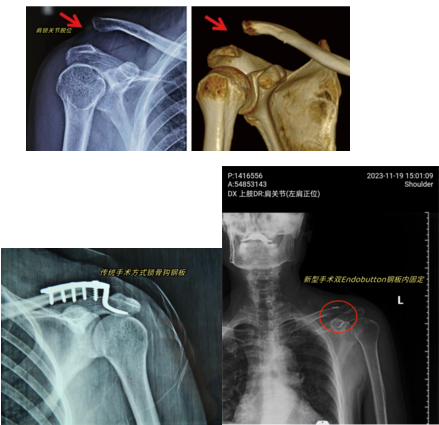

對(duì)于肩鎖關(guān)節(jié)脫位,傳統(tǒng)手術(shù)常常使用鎖骨鉤鋼板固定,一端固定鎖骨,另一端固定在肩峰下。不過,這種手術(shù)創(chuàng)傷比較大,而且鉤子在肩峰下長時(shí)間隨人體活動(dòng),會(huì)因?yàn)榉磸?fù)摩擦破壞骨質(zhì),可能導(dǎo)致肩關(guān)節(jié)疼痛、肩關(guān)節(jié)活動(dòng)受限、肩袖磨損、肩峰撞擊綜合征、再脫位等后果且活動(dòng)受限。所以一般來說放置的時(shí)間不能太長,半年左右之后就需要二次手術(shù)取出鋼板。

“這項(xiàng)手術(shù)方案是采用微創(chuàng)的方式放入兩個(gè)小如紐扣的鈦板,一個(gè)固定鎖骨,一個(gè)固定鎖骨下的喙突,中間用高強(qiáng)度的縫線連接,具備較好的穩(wěn)定性及療效,只需要一個(gè)3cm左右的小切口就能完成,大多數(shù)患者在術(shù)后立即就可以看到效果,同時(shí)可以將對(duì)肩關(guān)節(jié)的影響降到最低,后期也不需要二次手術(shù)取出!蓖踔魅蜗蚶先思覍俳榻B。

手術(shù)當(dāng)天,秦皇島市工人醫(yī)院骨二科王永述主任團(tuán)隊(duì),對(duì)常大爺進(jìn)行了左側(cè)肩鎖關(guān)節(jié)脫位切開復(fù)位雙Endobutton鋼板內(nèi)固定術(shù),手術(shù)時(shí)間40分鐘,出血僅10ml,手術(shù)切口僅3.5cm,手術(shù)成功完成。術(shù)后第四天患者已經(jīng)可以正常生活了,減少了患者的痛苦和經(jīng)濟(jì)壓力,術(shù)后取得了滿意療效,對(duì)此手術(shù)贊不絕口。